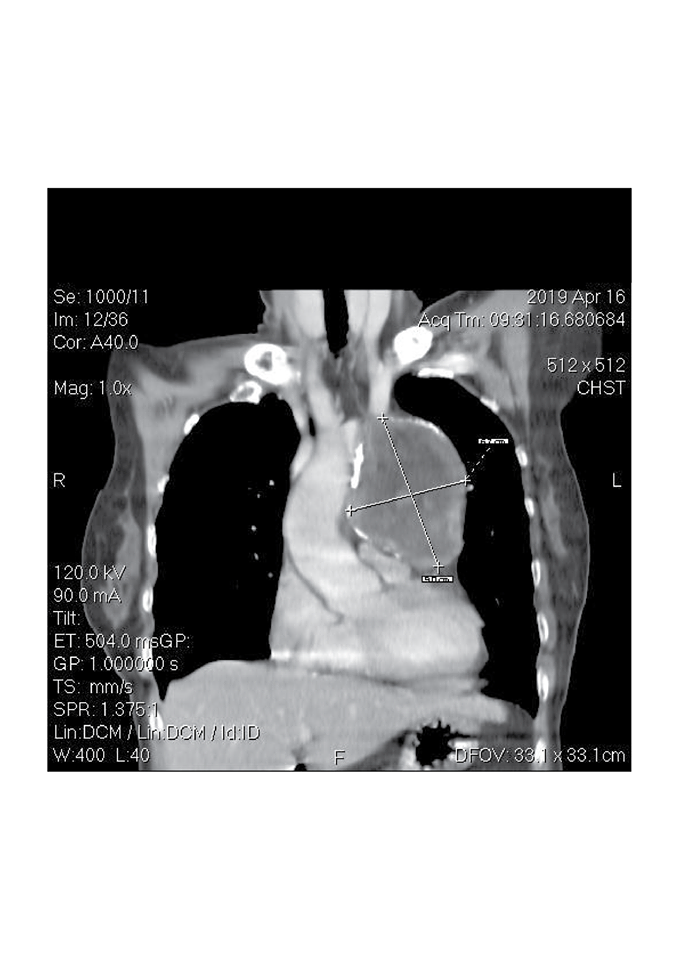

Tại Bệnh viện Medic Bình Dương, bệnh nhân đã được Bác sĩ chuyên khoa thăm khám và chỉ định đi chụp X- Quang ngực thẳng. Sau khi có kết quả, Bác sĩ nghi ngờ có dấu hiệu bất thường ở trung thất, đã hội chẩn và cho chỉ định chụp CT cắt lớp vi tính Lồng ngực kỹ thuật cao với máy CT Scanner 32 lát của hãng GE Mỹ 2017

Sau khi chụp CT, phát hiện có một khối choán chỗ trung thất trước to, làm cho bệnh nhân ho kéo dài, khó thở, tức ngực. Chẩn đoán đây là trường hợp U quái trung thất nên đã chuyển lên tuyến trên để phẫu thuật kịp thời.